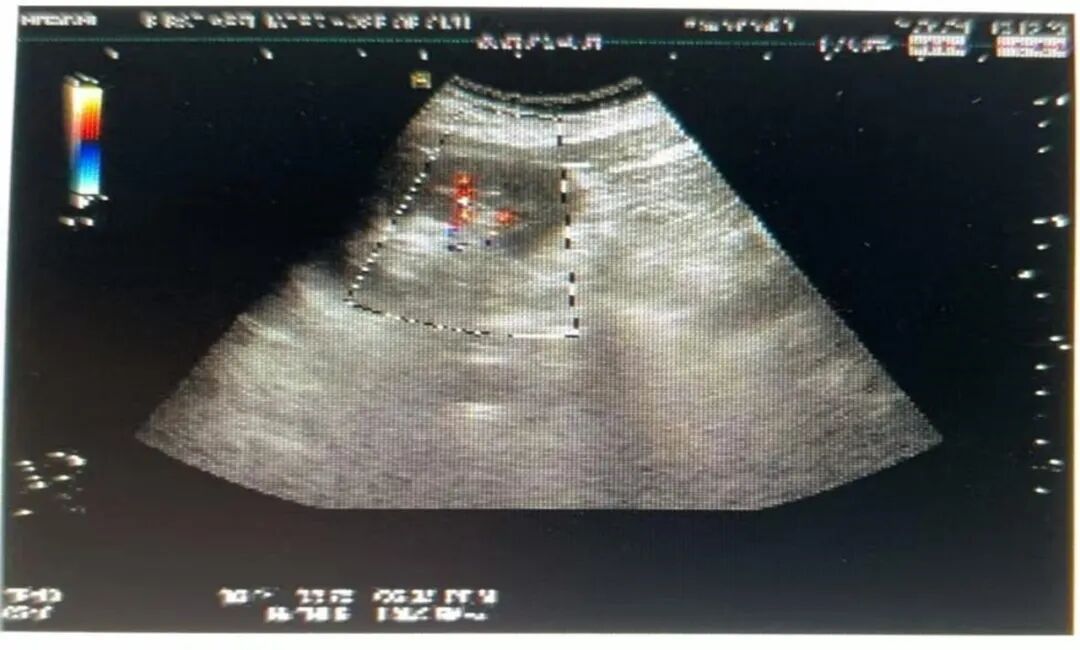

➣ 2021-01-24,超声:肝右叶切除术后,残余肝左叶形态稍饱满。